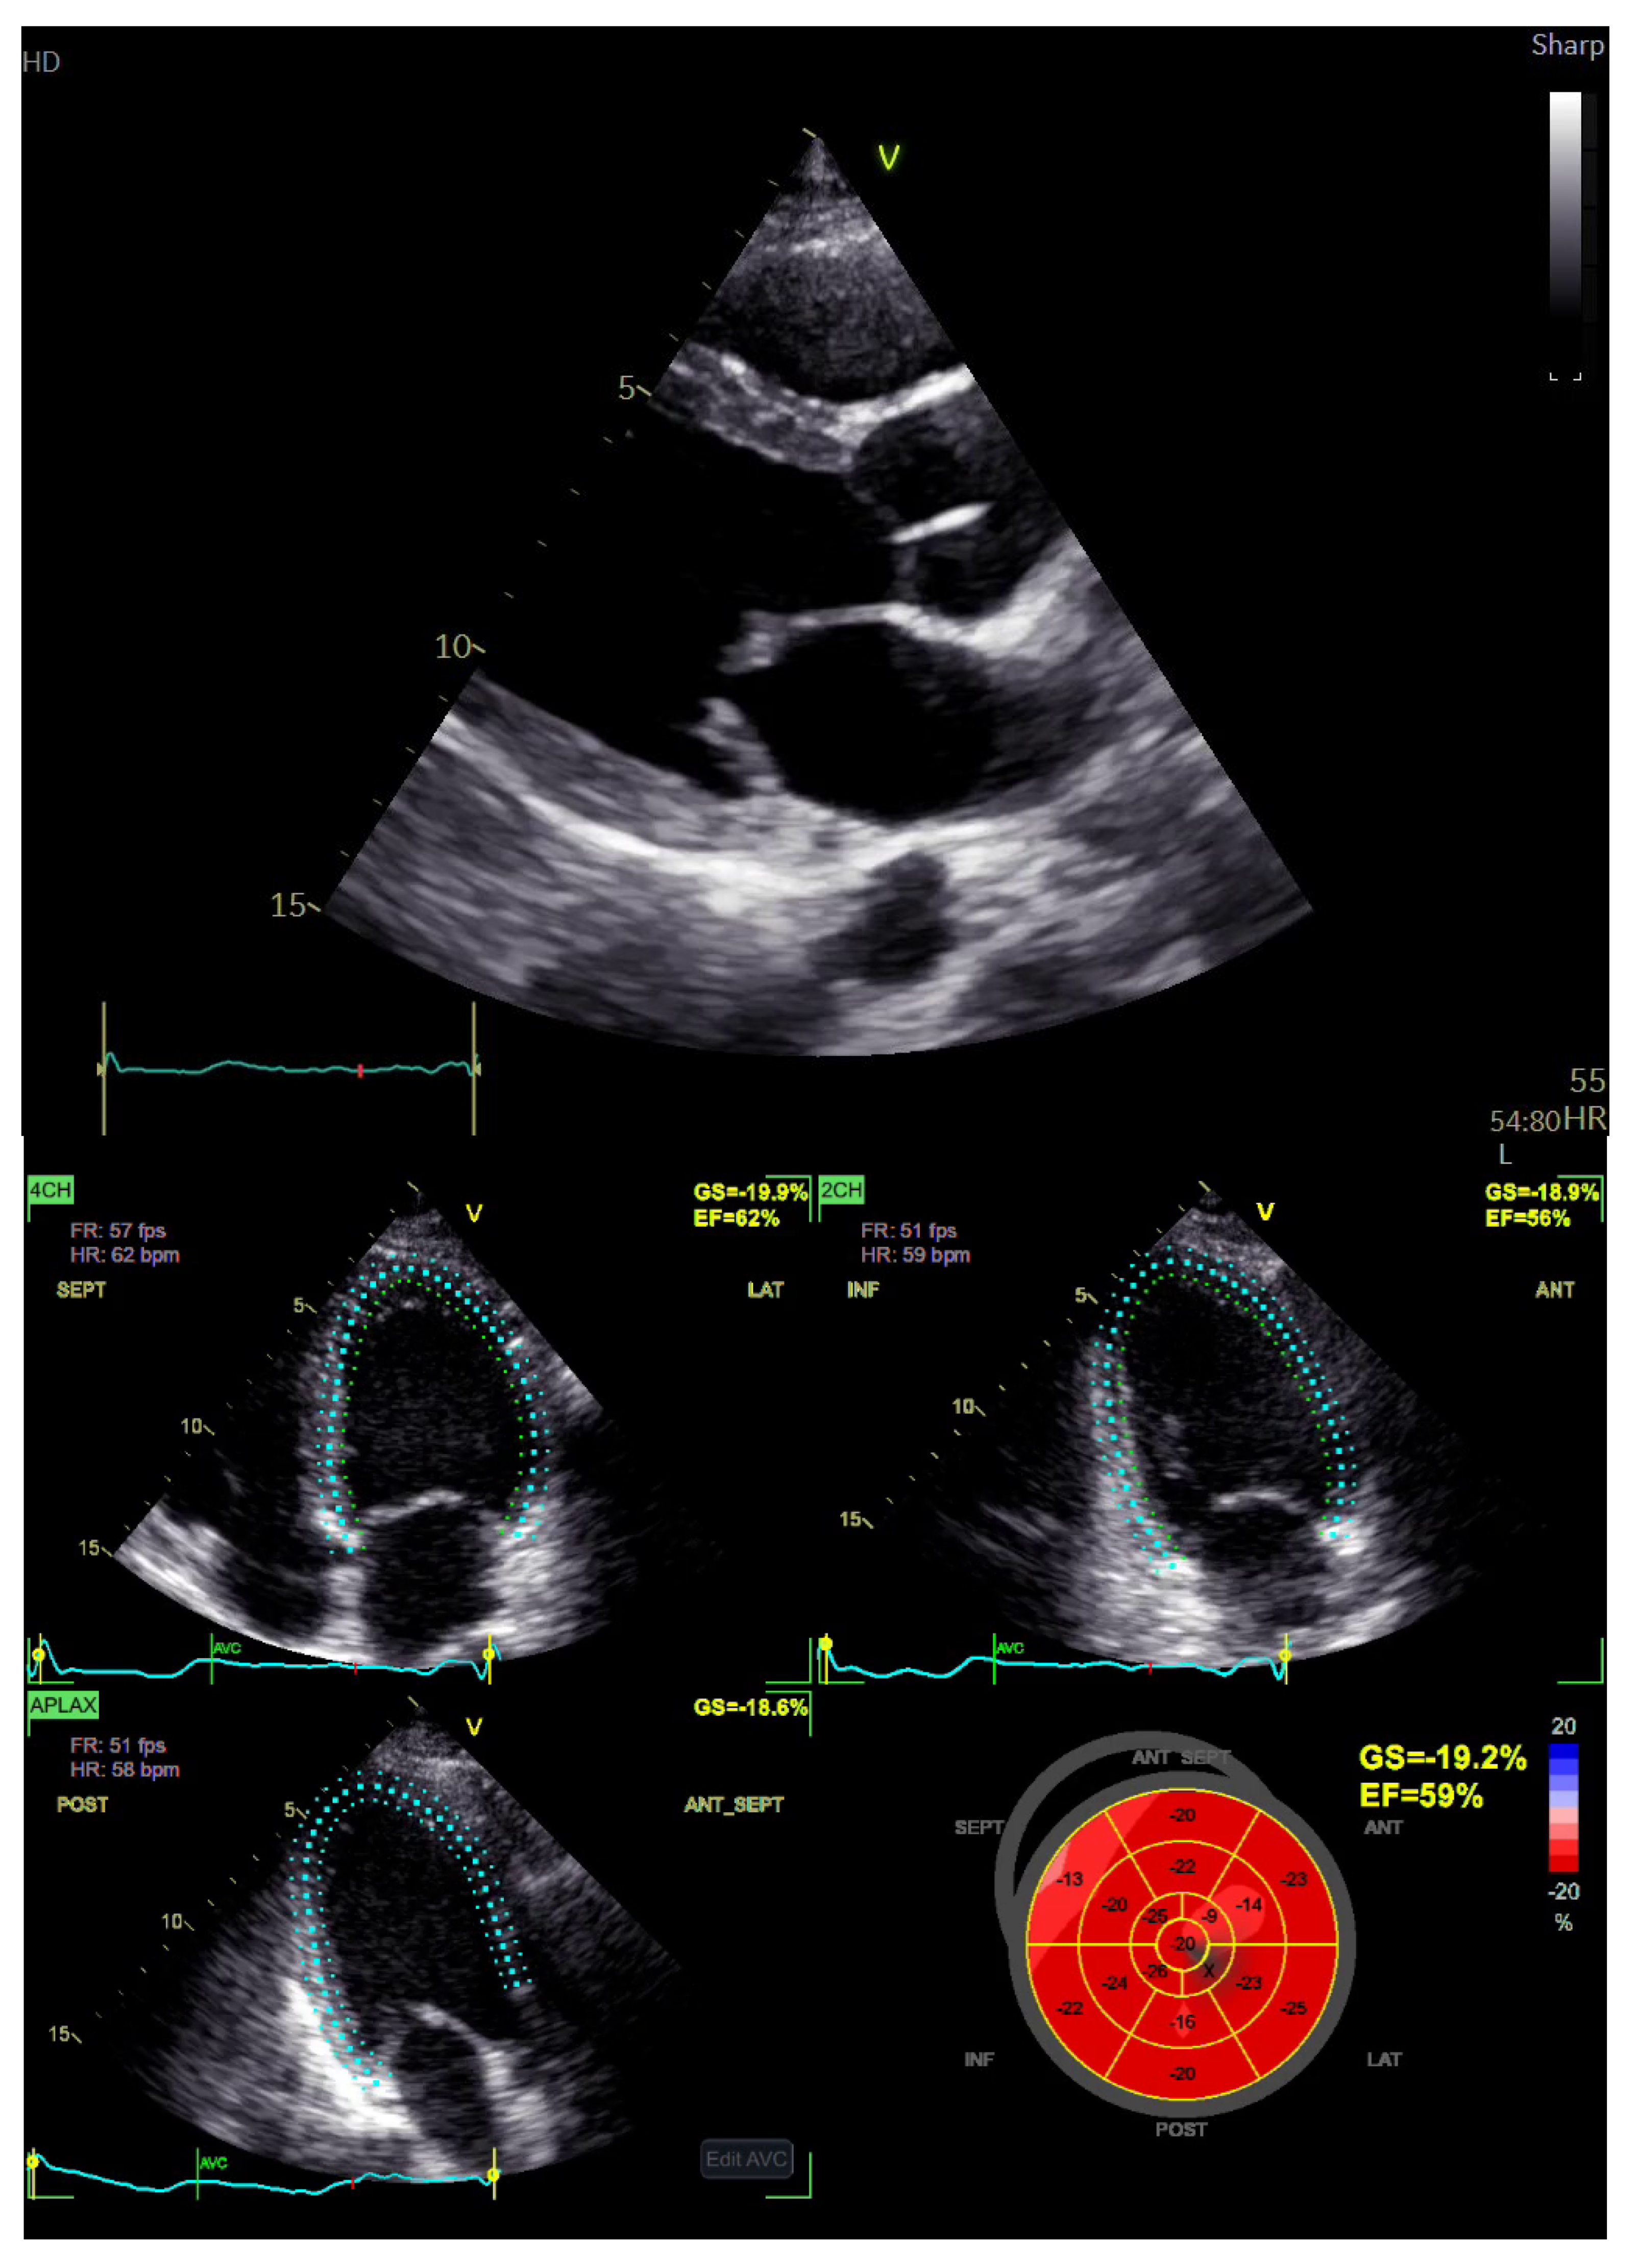

2. Case Report